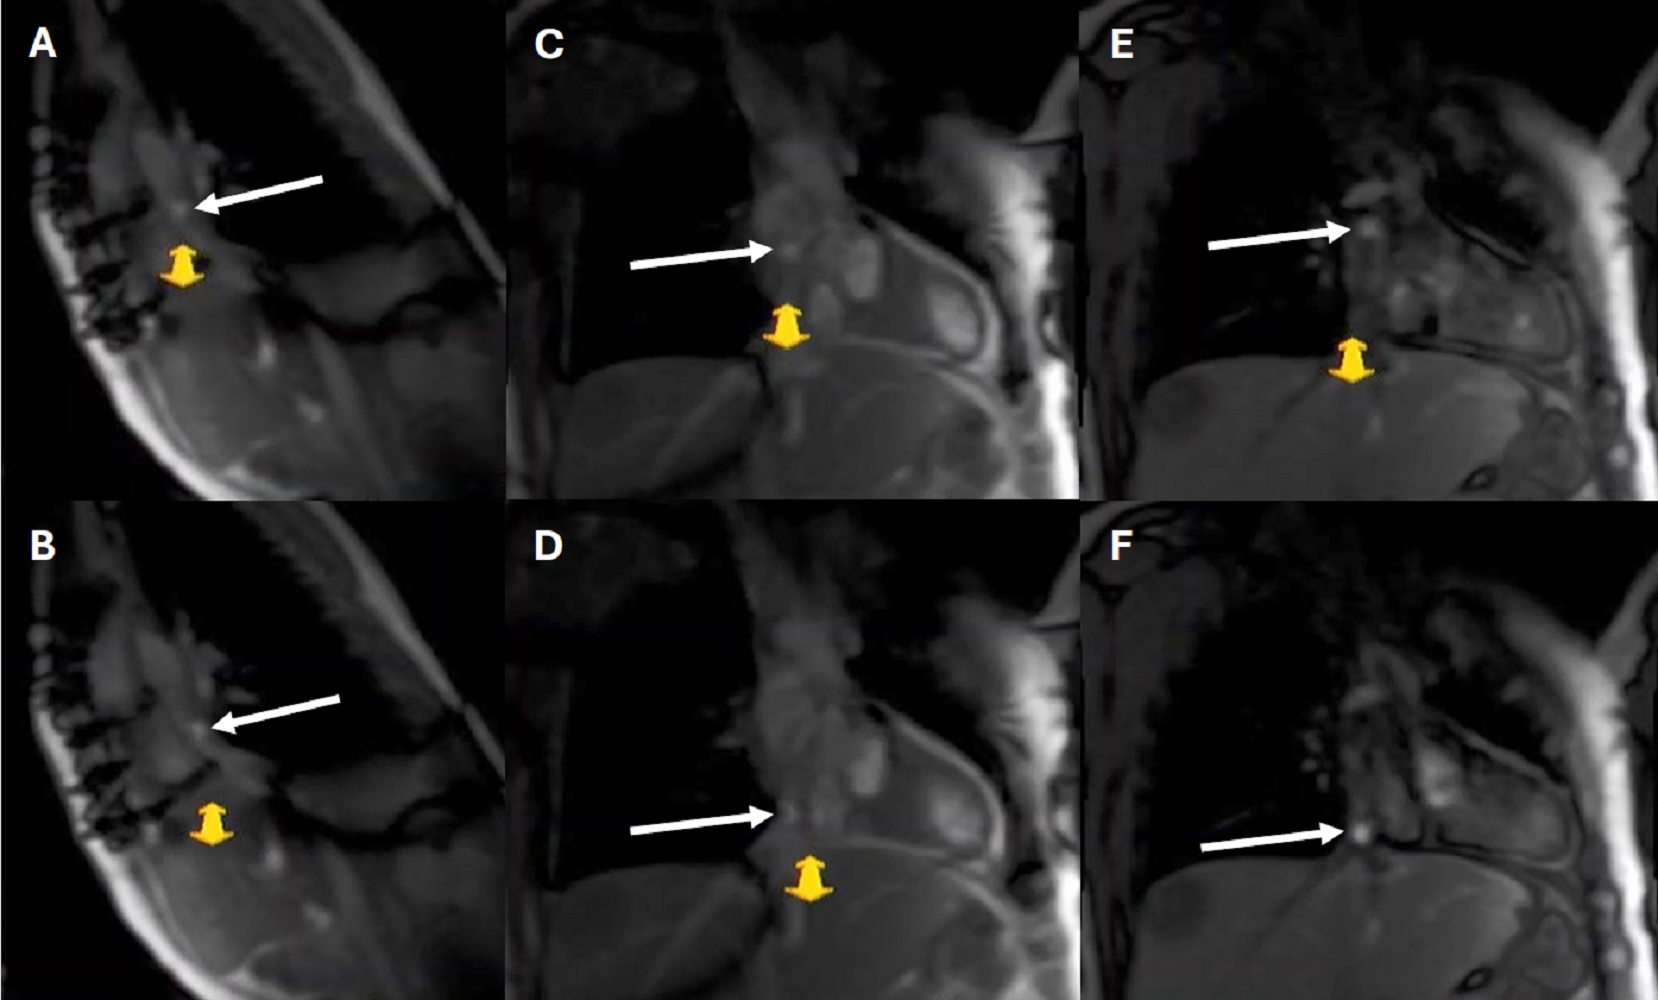

*On day of CMR/cath combo; BSA = body surface area; Cath = catheterization; CMR/cath combo = cardiovascular magnetic resonance catheterization combination; CHD = congenital heart disease; DORV = double outlet right ventricle; HLHS = hypoplastic left heart syndrome; iCMR = interventional cardiovascular magnetic resonance; MA = mitral atresia; PA = pulmonary atresia.Figure 1. Real time imaging with interactive framework (iDrive) to guide interventional cardiovascular magnetic resonance (iCMR) catheter movement. Balanced steady state free precession (A-D) and fast gradient recalled echo (E, F) images of a patient with single ventricle physiology status post Fontan. Images in a sagittal (A, B) and coronal (C-E) projection. The balloon tip catheter with diluted gadolinium solution (white arrows) appears hyperintense within the Fontan.